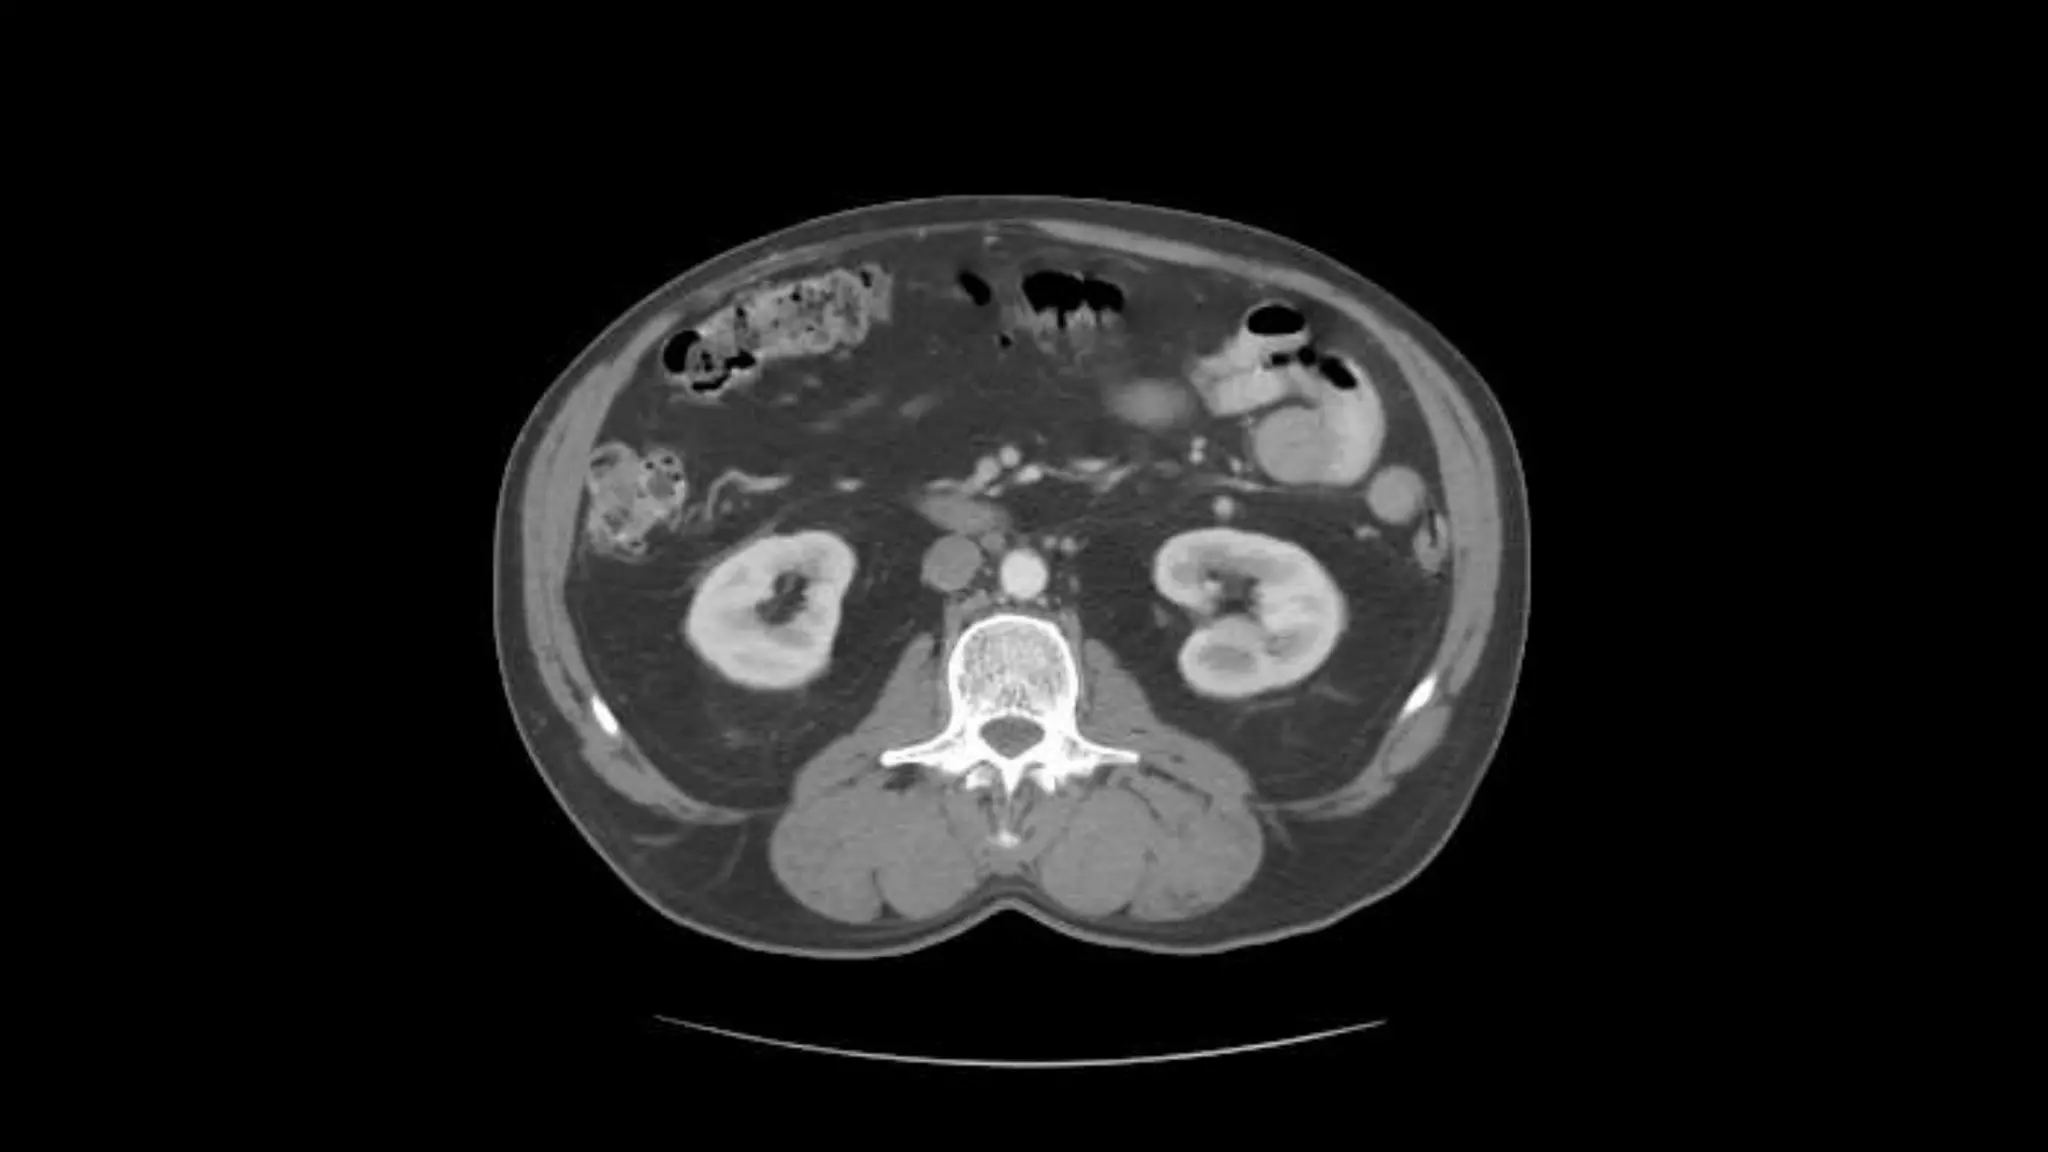

Renal Veins emptying into the IVC. We also see the right renal artery branching

off the Aorta, follow it down till you see it enter the right kidney. The Superior

Mesenteric Vein is outlined on the top of this image. If you follow the SMV up, you

will see it empty into the Portal Vein.

Here we see the right and left renal vein entering into the Inferior Vena Cava. We

Also see the left renal artery branching off the aorta and heading toward the left

kidney. Page up and down to trace these vessels.

Superior Mesenteric Vein – follow it up as it joins the Splenic

Vein to form the Portal Vein

Renal Veins emptyinginto the IVC. We also see the right renal artery branching off the Aorta, follow it down till you see it enter the right kidney. The Superior Mesenteric Vein is outlined on the top of this image. If you follow the SMV up, you will see it empty into the Portal Vein.

• 33.

Here we seethe right and left renal vein entering into the Inferior Vena Cava. We Also see the left renal artery branching off the aorta and heading toward the left kidney. Page up and down to trace these vessels.

• 34.

Superior Mesenteric Vein– follow it up as it joins the Splenic Vein to form the Portal Vein